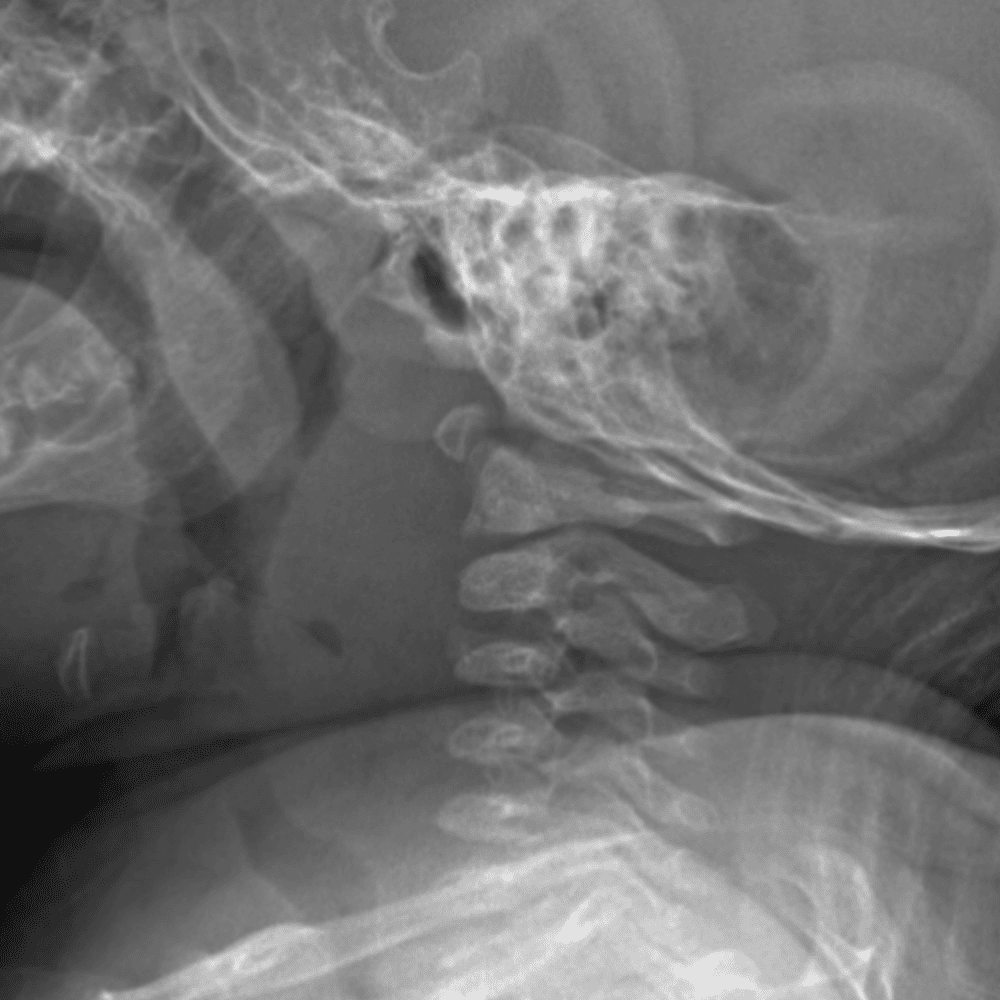

Peds Chest

Practice

Simulates call by including subtle or difficult cases and some normals.

50 cases